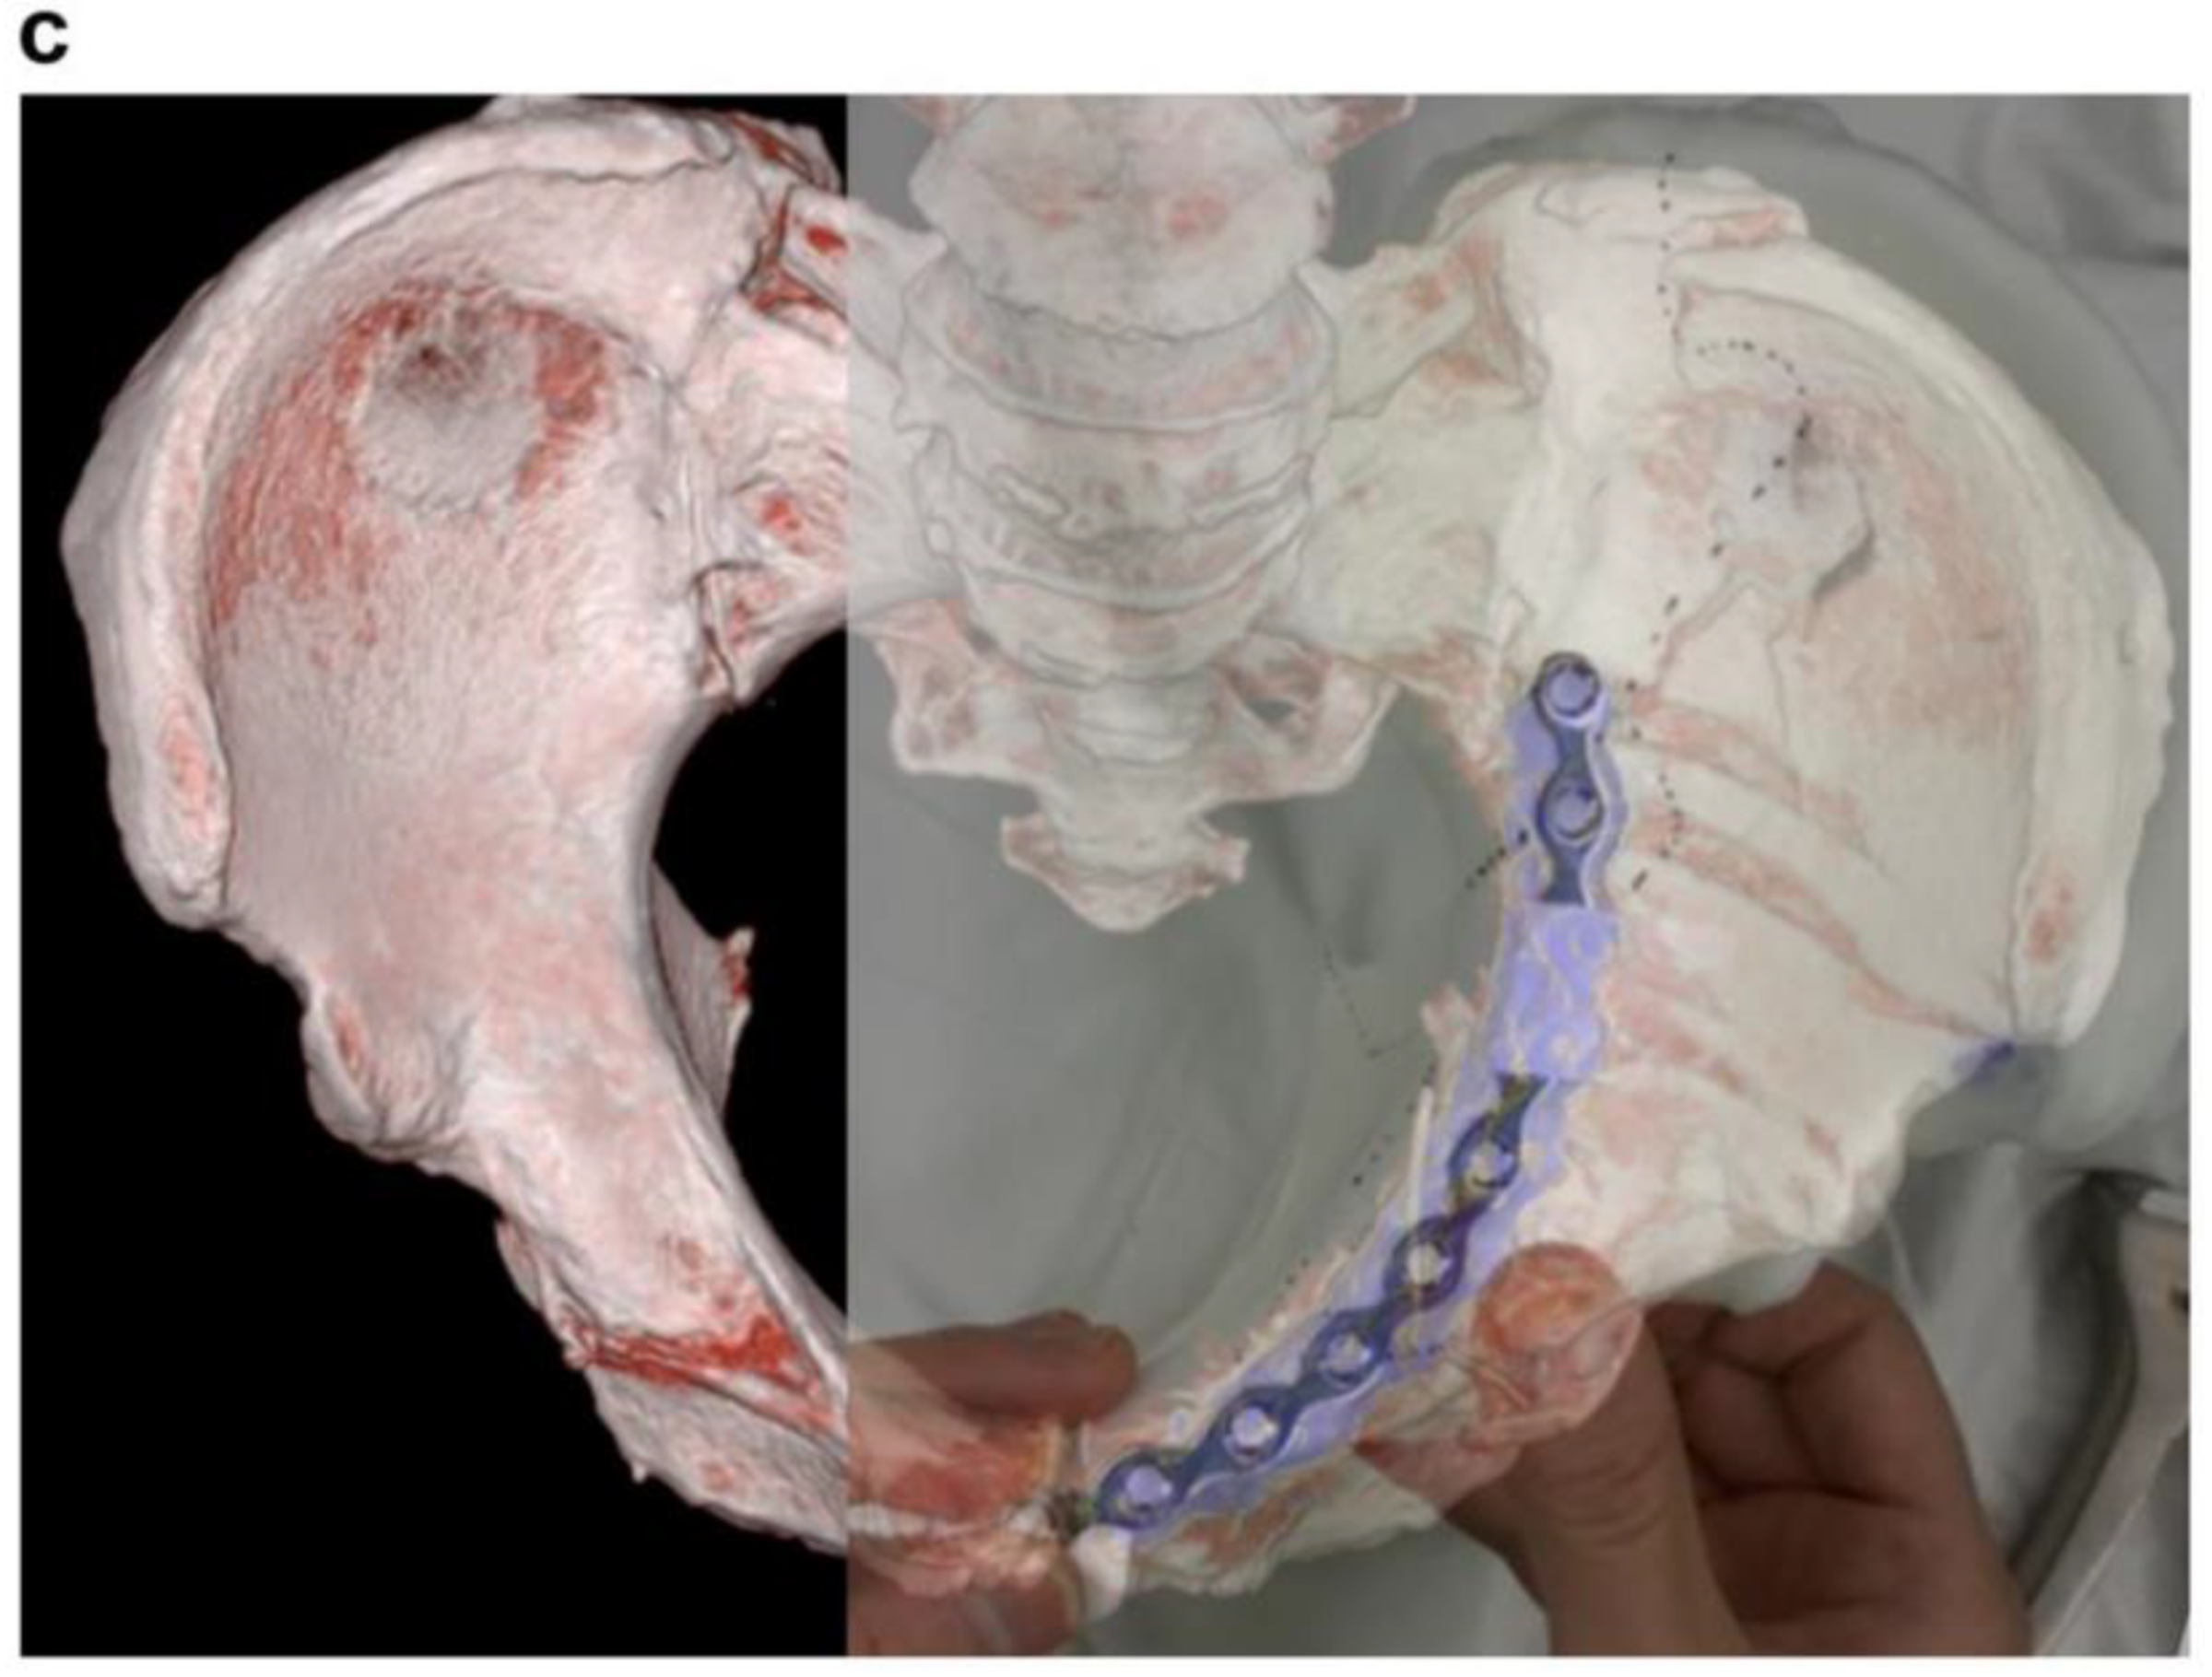

- Sakong, S.-Y.; Cho, J.-W.; Kim, B.-S.; Park, S.-J.; Lim, E.-J.; Oh, J.-K. The Clinical Efficacy of Contouring Periarticular Plates on a 3D Printed Bone Model. J. Pers. Med. 2023, 13, 1145. [Google Scholar] [CrossRef]